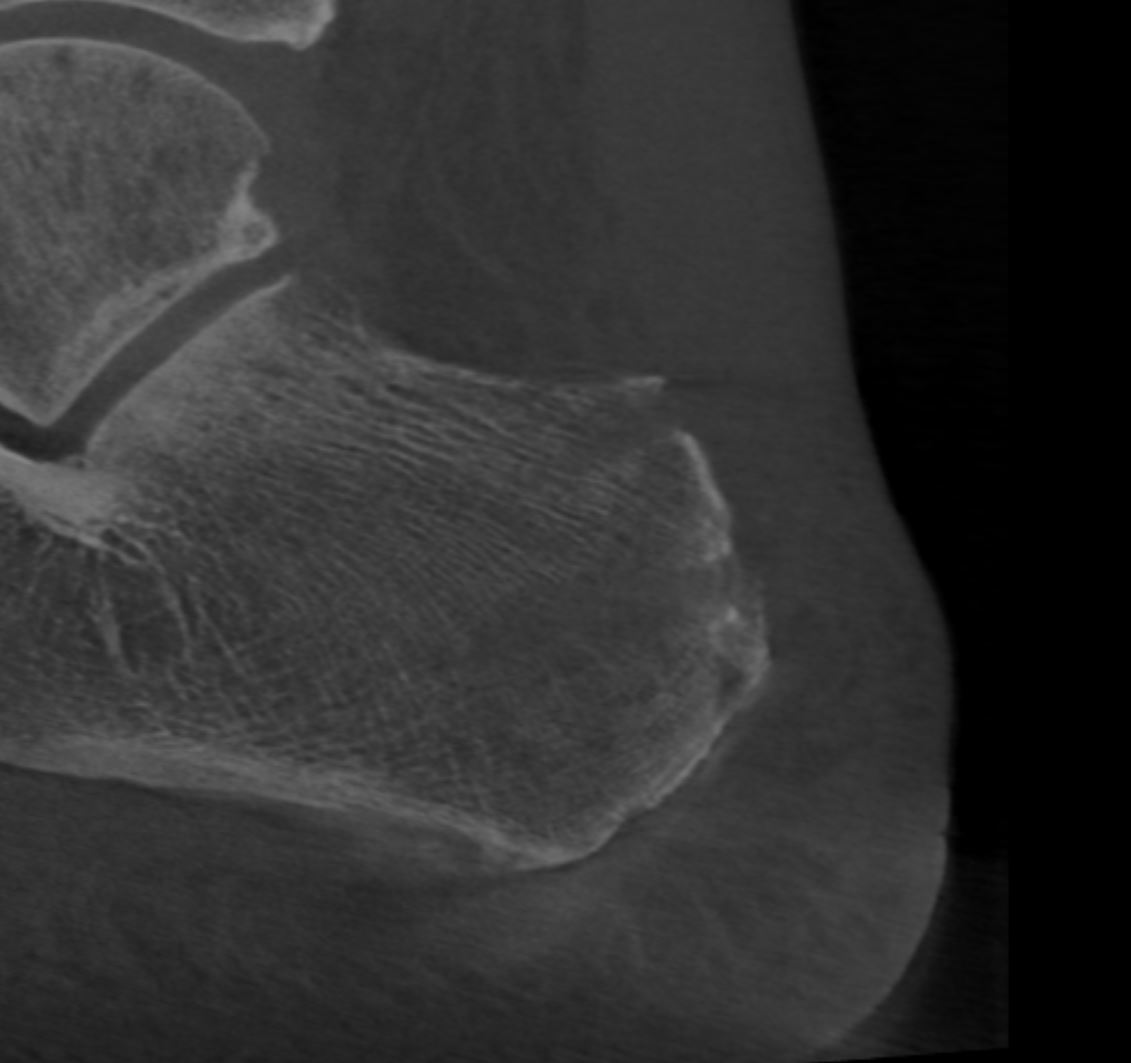

Home Schwerpunkte Krankheitsbilder Haglund-Syndrom & Haglundferse Haglund Syndrom nach der Operation

Haglund Syndrom nach der Operation